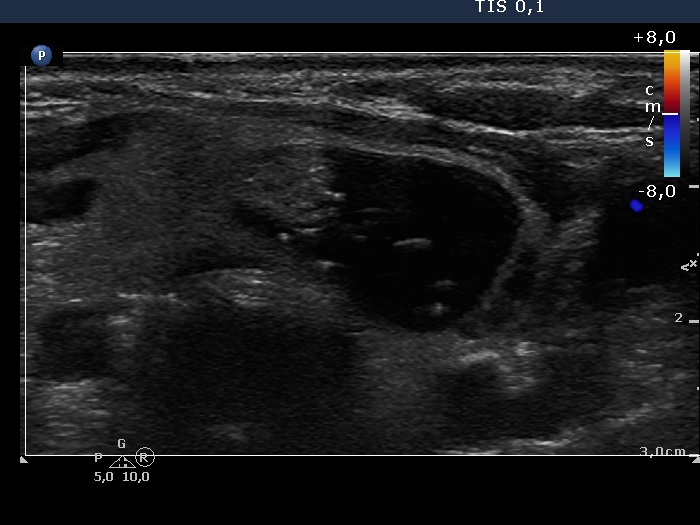

Study on 100 consecutive patients with thyroid nodule - case 029 (ultrasonographic picture 9)

Left lobe, transverse scan, color Doppler mode.